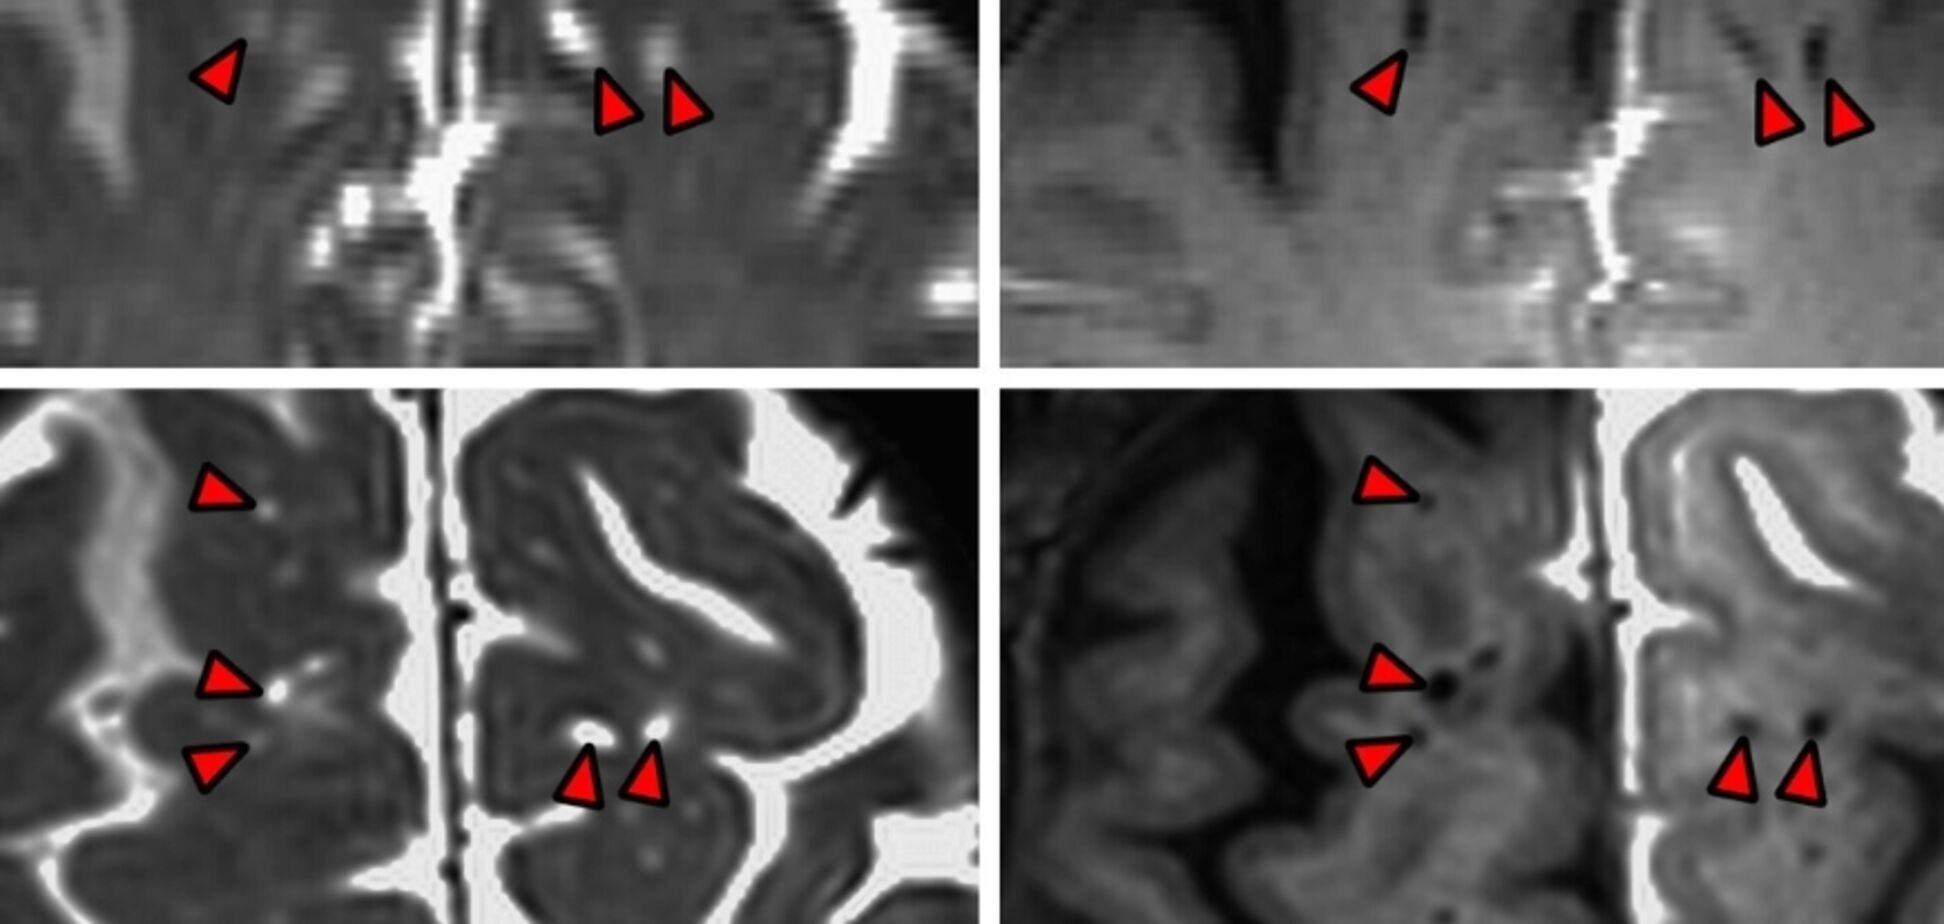

Дослідження стало можливим завдяки згоді п’яти дорослих людей, які перенесли операцію на головному мозку і їм потрібно було ввести ліквор для процедури. Тож перед заміною рідини вчені позначили її темним контрастним маркером. Пізніше спеціальний тип магнітно-резонансної томографії відобразив місце, де рідина пішла в мозок учасників дослідження.

Отримані дані свідчать про те, що людський мозок не поглинає спинномозкову рідину безладно, як губка. Натомість рідина проникає глибше в неврологічну тканину та йде слідами кровоносних судин.

Вчені наголошують, що канали спинномозкової рідини не є застійними, заповненими рідиною структурами, а функціональними. Вони сприяють "розповсюдженню СМР у мозку".